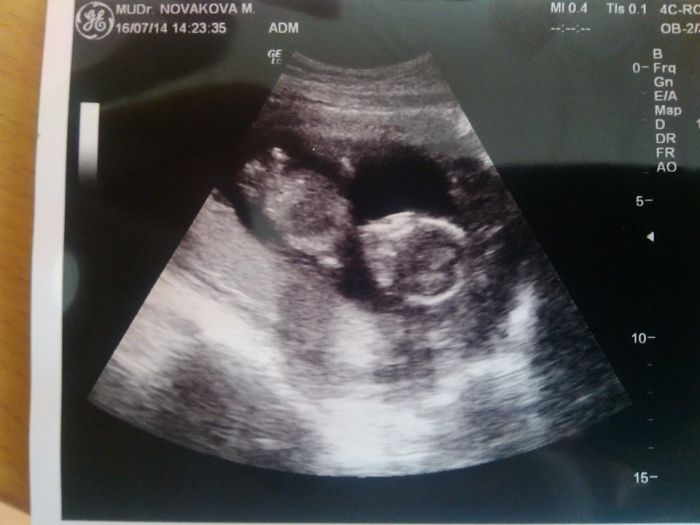

Jiřinko,gratuluji ke zdárnému screeningu a krásné fotečce mimča.